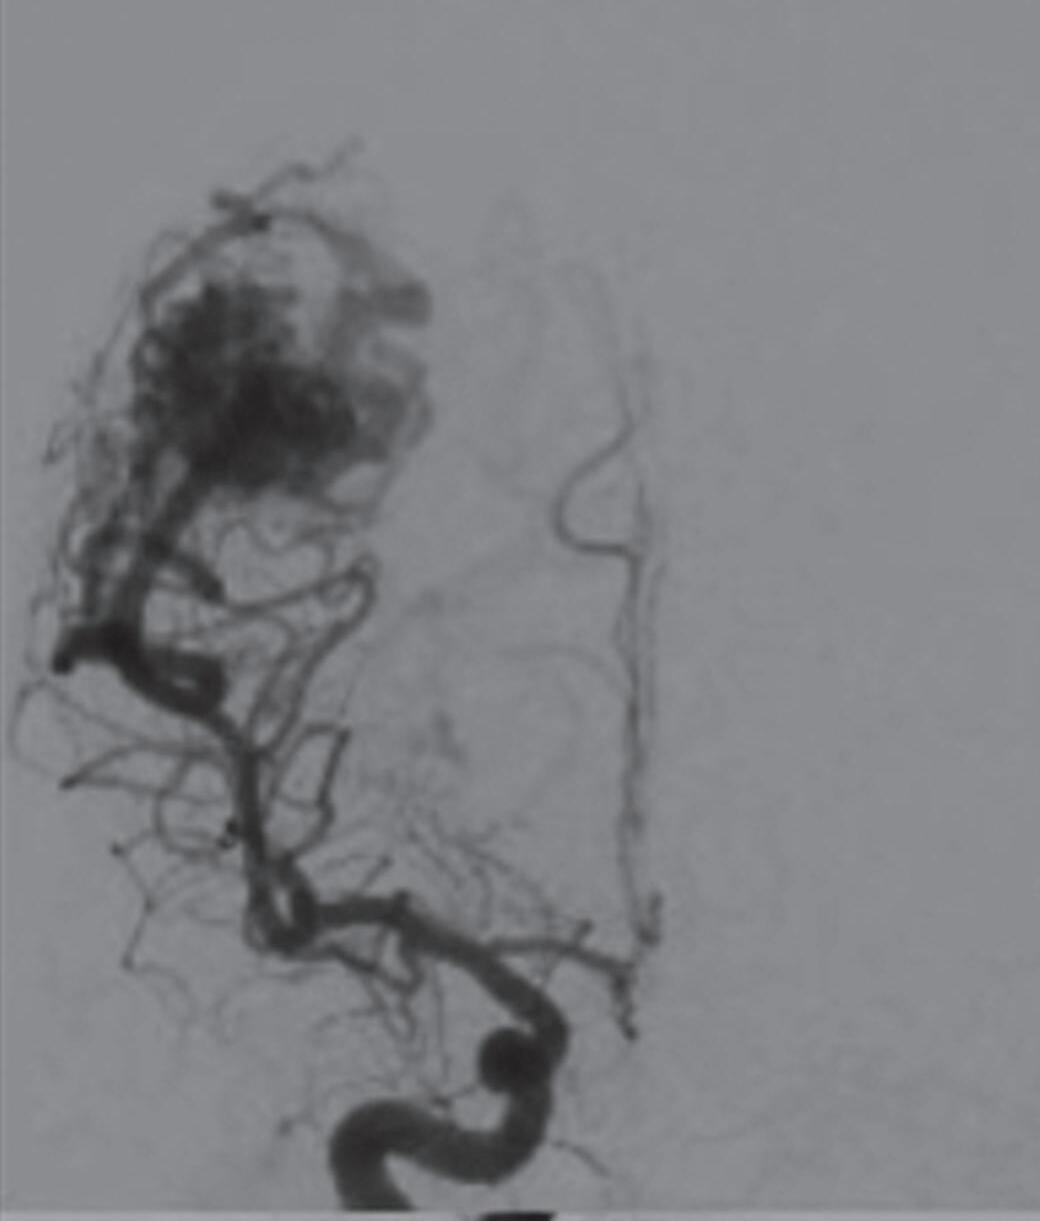

Fig. 1-8. (a-c) RNM T1 com contraste, cortes sagital (a), coronal (b) e axial (c) demonstrando MAV não rota com nidus localizado no lobo occipital à esquerda (setas longas). (d) Arteriografia digital cerebral com injeção de contraste via carótida direita (AP) mostrando a contribuição da carótida direita na irrigação da MAV contralateral. (e,f) Com injeção de contraste via carótida esquerda, em Perfil e AP respectivamente, observa-se nidus compacto nutrido por ramos da artéria cerebral média à esquerda e a veia de drenagem precoce se dirigindo para o seio sagital superior. Projeções em AP (g) e em perfil (h) demonstrando a contribuição do sistema vertebrobasilar por meio de ramos distais da artéria cerebral posterior à esquerda e drenagem para os seios sagital superior e sigmoide à esquerda (setas curtas).